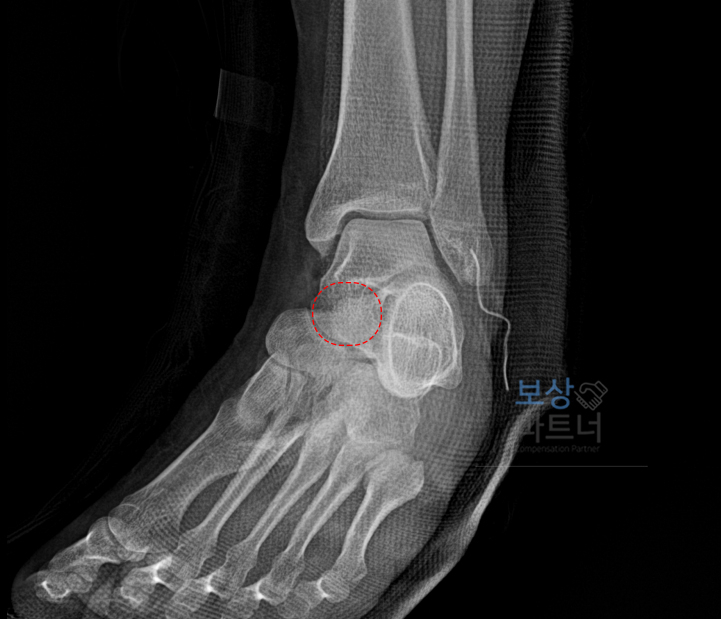

병원에서 X-ray 검사를 받은 결과, 좌측 발목 염좌 및 인대의 파열이라는 진단을 받게 됩니다. 주상병: 요추의 염좌 및 긴장, 발목 및 발 부위의 인대 파열 상세 진단: 좌측(Lt.) 전거비인대 파열

image

특히 영상 검사(X-ray 등)와 정밀 진단 결과, 파열의 정도가 심해 수술적 치료를 시행하셨으며, 치료 이후에도 발목 관절의 움직임이 제한되는 부전 강직(운동 제한) 소견이 확인되었습니다.